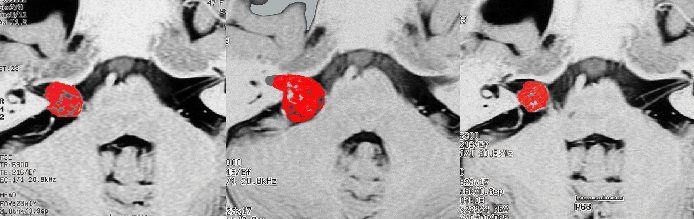

定位分割放射線治療をした聴神経腫瘍の例(左)。20%くらいの確率で放射線治療後に一時的に大きくなることがあります(中央)。やがて小さくなっていきます(右)。放射線治療後に腫瘍が大きくなっても,あわてて手術を受け入れてはいけません。

この画像はMRIのCISS/FIESTA画像というのを用いています。造影剤を使わないでも腫瘍の形と大きさが精密に解るので,経過観察には適している検査法です。

2001年に治療をした,40代女性の大きな聴神経腫瘍です。50グレイ25分割の定位放射線治療を行いました。中央が1年後,右が3年後です。徐々に縮小して手術を必要としませんでした。このサイズの聴神経腫瘍でも放射線治療は選択できるのですが,多くの場合は開頭手術をお勧めするサイズとも言えます。